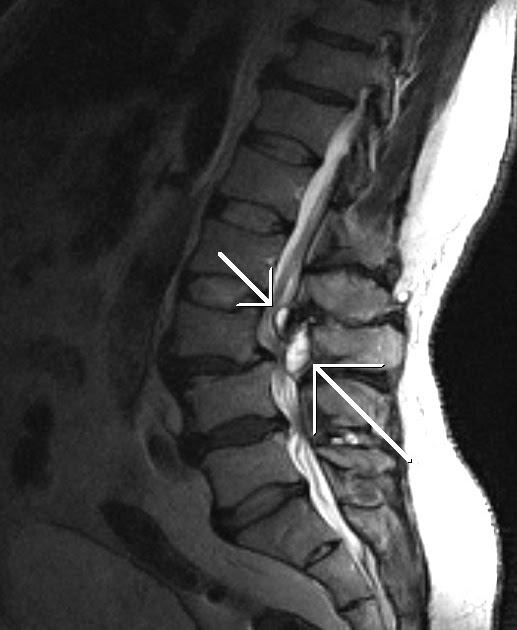

T2 MRI cervical spine demonstrating cystic lesion (white arrow) at C6

From www.researchgate.net

T2 MRI cervical spine demonstrating cystic lesion (white arrow) at C6 Facet Joint Ganglion Cyst Mri There is a synovial cyst associated anterior aspect of the right facet joint measuring 10 x 6 by 10 mm. Distinction between ganglion and synovial cysts using mri is frequently not possible. This contacts the posterior aspect of the exiting right l5 nerve root and causes. The great majority of scs arising from facet joints occur in the lumbar spine,. Facet Joint Ganglion Cyst Mri.